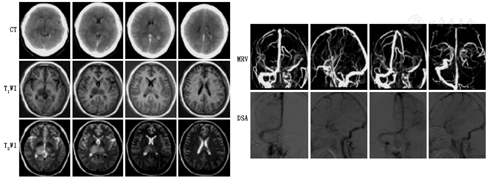

DSA是在脑血管中(动脉和静脉均可)注射造影剂,然后进行系统处理,使血管显示地更加清晰,便于医生诊断或进行手术。DSA所需的造影剂量少、浓度低、X线吸收量少,而对比度分辨率高,可展现脑部所有血管(颈内动脉系统和椎动脉系统)不同部位、不同狭窄程度的管腔及不同部位、不同大小的动脉瘤等(图10,图11),是脑血管病变检查的"金标准"。

PCoA:后交通动脉;ACoA:前交通动脉;MCA:大脑中动脉;PCA:大脑后动脉

DSA可用于各种目的的脑血管检查,包括脑血管病的病因检查,如颈部血管和脑血管狭窄、动脉瘤、动脉夹层(图12)、静脉血栓形成、动静脉瘘等;急诊动脉取栓、动脉溶栓以及脑动脉狭窄支架的介入治疗。

"一站式"多模态CT由NCCT、CTP及CTA组成(图13),目前应用广泛,方便快捷,为动脉取栓、动脉瘤介入或外科手术提供精准诊疗。NCCT可鉴别患者是否存在脑出血;CTA可以鉴别是否有动脉瘤或大血管闭塞;CTP可以提供脑血流的灌注情况、是否存在半暗带、侧支循环及血脑屏障完整性等信息,为进一步制定患者的诊疗方案,判断预后奠定基础。